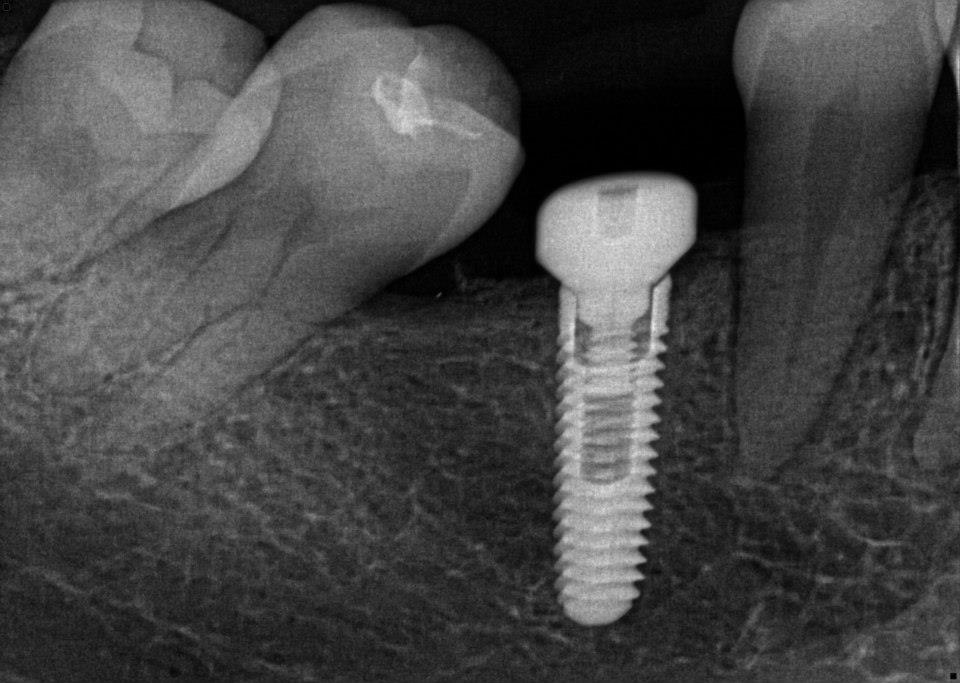

အယင္က သြားစိုက္တဲ့ဆီမွာ ရွိျပီးသားသြားကို crown စြတ္ေပးတာ၊ အံပုံတပ္ေပးတာ၊ ေဘးက သြား ၂ ေခ်ာင္းကို ပိုးျပီး ၾကားမွာ သြားအတုကို bridge လုပ္ေပးတာေတြ လုပ္ေလ့ရွိရာက ေနာက္ပိုင္းမွာ သြားကို သြားဖုံးေအာက္က အရိုး (ေမးရိုး) ထဲမွာ titanium မူလီကို ထည့္သြင္းျပီးအေပၚကေန သြားအတု စိုက္ေပးတဲ့ ေခတ္ေပၚ နည္းပညာစနစ္ကို သုံးစြဲလာၾကတယ္လို႔ ဆိုပါတယ္။

ေမးရိုးထဲမွာ တိုင္ေတနီယံသံေခ်ာင္းကို ထည့္သြင္းျခင္း၊ လူရဲ့ အရိုးမ်ားက အဆိုပါပစၥည္းကို လက္ခံသည့္ တုန္႔ျပန္႔မႈေကာင္းျခင္း၊ ၎အေပၚက သြားတုကို တပ္ဆင္ျပီးေနာက္ သြားတု၏ တုန္႔ျပန္မႈ၊ ထိေတြ႔မႈတို႔မွာ လူနာအတြက္ အေႏွာက္အယွက္မျဖစ္ျခင္းတို႔ေၾကာင့္ ရိုးရိုးသြားတုမ်ား တပ္ဆင္တာထက္ ယခု DENTAL IMPLANT က သြားစိုက္သူမ်ားအတြက္ သင့္ေတာ္တဲ့ ေရြးခ်ယ္မႈ ျဖစ္လာတယ္လို႔ ဆိုပါတယ္။